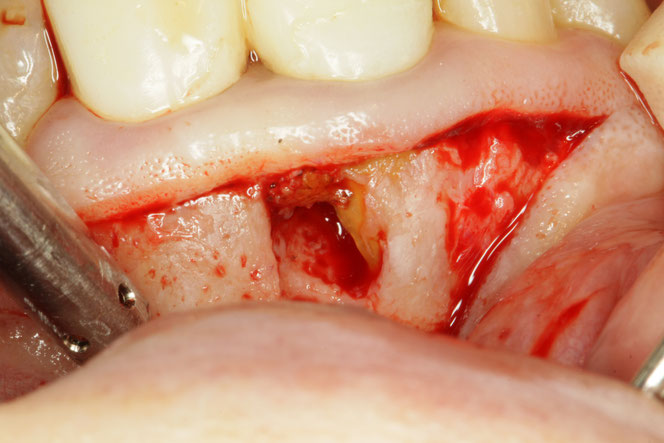

歯ぐきの再生療法は、結合組織移植術、歯冠側移動術といった歯周形成外科と言われている方法で行います。下がってしまった歯茎を元の状態に近づけ、再発を予防する方法です。

歯茎の再生治療は、歯茎の移植を伴う外科的な治療ですので、治療後に糸でしっかりと縫う必要があります。尖ったものが刺さってしまったりして歯茎が開くと出血してしまうリスクがあります。また、術後の腫れや痛みが出る可能性があります。

歯茎の再生治療のリスクと対策

歯茎の再生治療は外科的な治療ですので、治療後に糸でしっかりと縫う必要があります。尖ったものが刺さってしまったりして歯茎が開くと出血してしまうリスクがあります。また、術後に腫れや痛みが出ることがあります。そのため、当院では、出血予防止血対策にに止血用マウスピースをお渡ししております。また、術後の注意を守っていただいております。